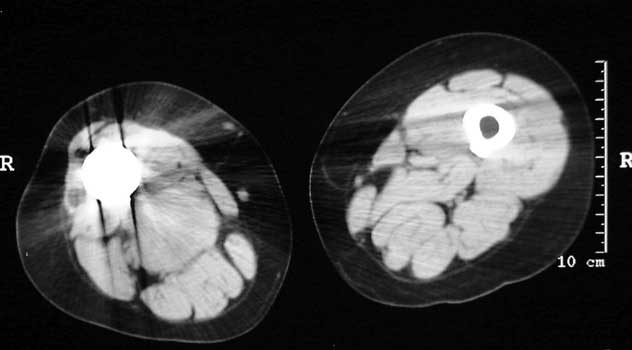

Mass in patient with modular endoprosthesis placed after resection of femur for osteosarcoma. Axial (fig A) and coronal reformatted images (fig B) clearly demonstrate mass adjacent to modular endoprosthesis. 14 gauge core needle biopsy performed under CT guidance (fig C) demonstrated recurrent osteosarcoma

Recurrent osteosarcoma in patient status post resection of femur and placement of modular endoprosthesis. Axial T1 and STIR sequences clearly demonstrate mass adjacent to endoprosthesis.